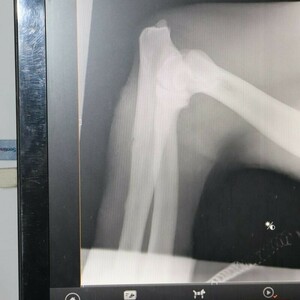

В ночь на 14 февраля в посёлке Андреевка Хасанского района был отловлен самец амурского тигра. В центре «Тигр» был проведён ветеринарный осмотр хищника – это взрослый самец 5-7 лет, весом 168 килограммов. Обнаружены множественные раны мягких тканей различной давности – старые воспалённые, а также свежие. Предположительно, это раны от схваток с другими тиграми.

Фото: VL.RU, центр «Тигр».